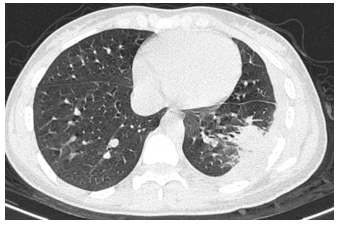

Pulmonary Hydatid Cyst with Broncho-Pleural Rupture: A Rare Complication to be Considered (Case Report)

Ali Haidar, Ahmed El Mostarchid, Lina Blekouchi, Nazik Allali, Siham El Haddad and Latifa Chat. 13(8): 01-04.